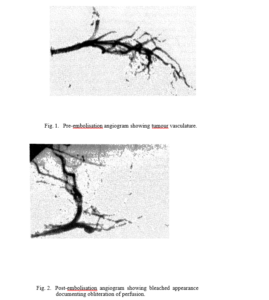

8. An early experience with AK-2123 administered

intra- arterially in the treatment of recurrent

hemorrhaging of cervix. 60

N.G Huilgol C.KK. Nair, Rohit Mathew and

Neela A. Chatterjee